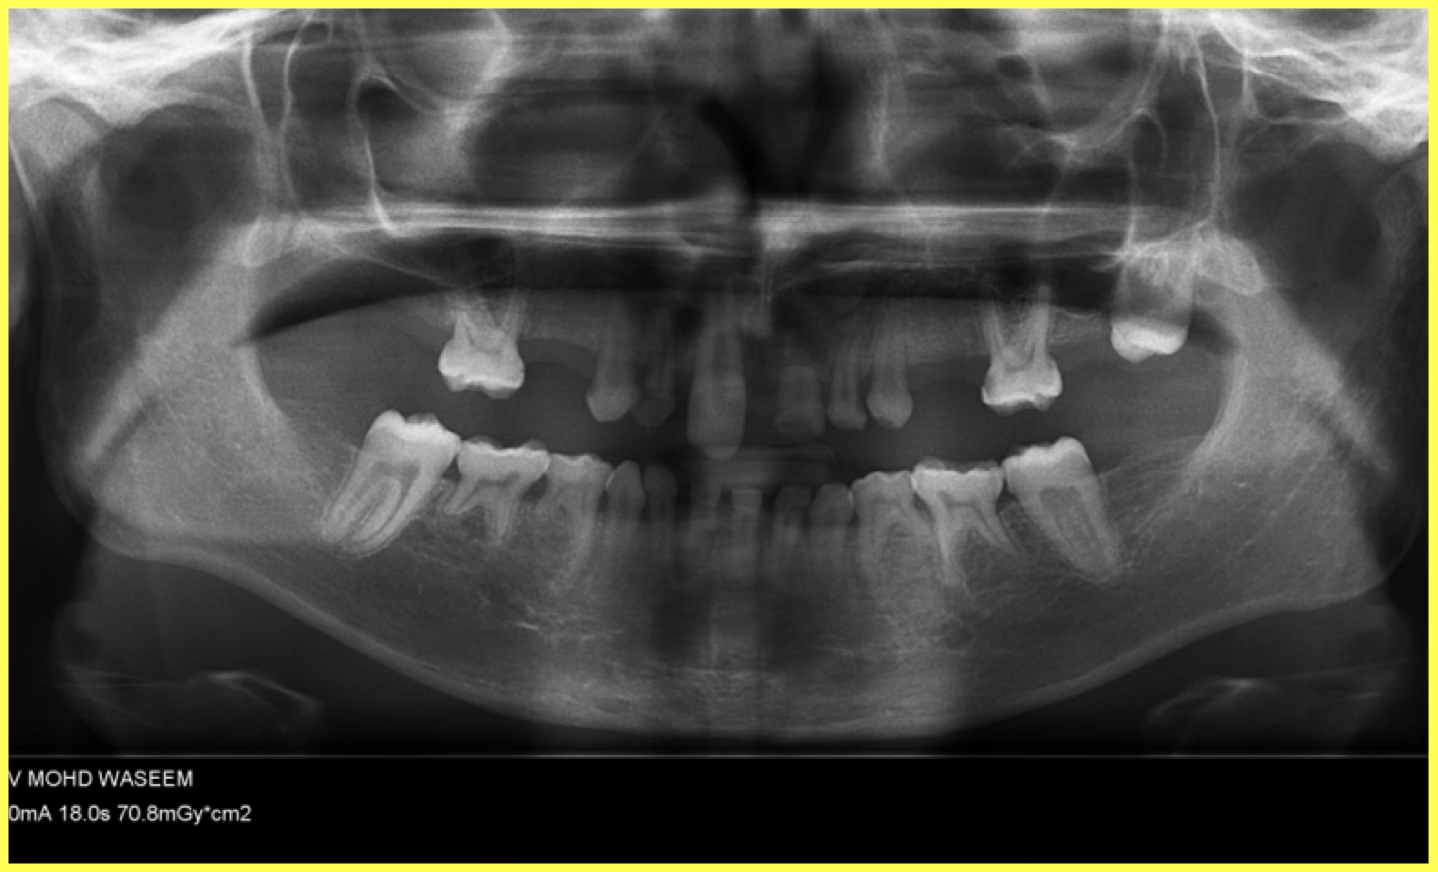

A 13-year-old male patient presented with oligodontia (congenitally missing permanent teeth) and retained deciduous (milk) teeth. Only two permanent lower molars were present. Treatment involved root canal therapy for all existing teeth followed by telescopic removable metallic PFM prosthesis for complete rehabilitation.

Comprehensive oral examination and OPG X-ray revealed oligodontia with only two permanent lower molars present. Patient had multiple retained deciduous teeth with aesthetic and functional concerns.